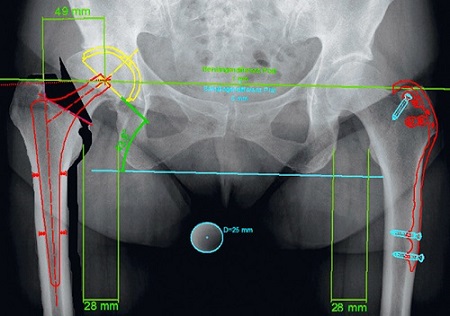

3. Xác định độ bù chiều dài của chân trước và sau phẫu thuật và hiển thị trực quan bằng hình ảnh.

MediCAD 2D Hip tạo điều kiện thuận lợi cho việc trao đổi phục hình bằng cách hiển thị các mô cấy đã được cấy ghép.

5. Xác định chênh lệch offset của xương đùi hai bên

Các thuật toán đo lường mới với sự hỗ trợ của máy tính đã được thiết lập để hỗ trợ bác sĩ phẫu thuật trong quá trình thay toàn bộ khớp trong mổ. Bác sĩ có thể đánh giá chiều dài chân và độ lệch được đo bằng hệ thống định vị đáng tin cậy trong quá trình tạo hình khớp háng .

Ước tính đền bù xương đùi. Độ di lệch xương đùi được định nghĩa là khoảng cách giữa trục dọc ở giữa của xương đùi đến tâm xoay của khớp háng.